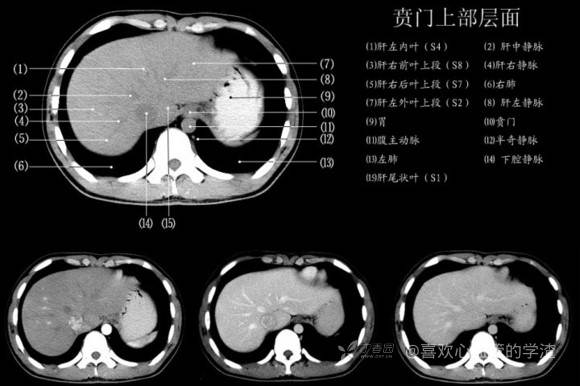

其实你离掌握上腹部 CT 影像只有一套高清实用图谱的距离,下面把我最喜欢的这本图谱分享给大家,为了方便阅读,我加了中文标识。后面附赠几张血管相对位置解剖关系图片,帮助大家理解(文中多图,建议在 wifi 环境下查看)。